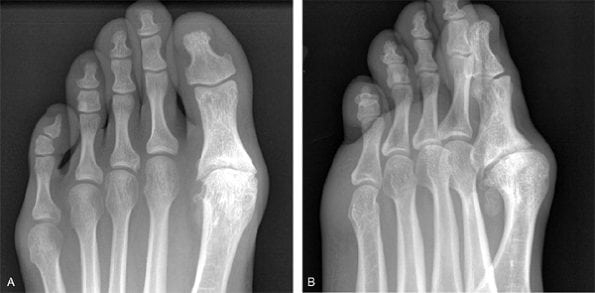

Опытной диагност заподозрит развитие плюснефалангового артроза при внешнем осмотре стопы. На патологию указывают развивающаяся вальгусная деформация, отечность большого пальца, подгибание стопы при ходьбе. Для подтверждения диагноза проводятся инструментальные исследования. На рентгенологических снимках заметны сформировавшиеся остеофиты, уменьшение размера суставной щели, обызвествленные участки. При необходимости назначается КТ или МРТ. Эти методы наиболее информативны для обнаружения поражений связок, мышц и сухожилий. Проводятся и лабораторные исследования: